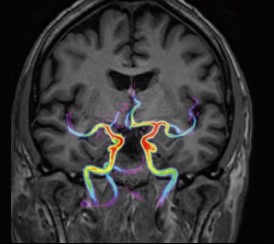

Uchwyć hemodynamikę w bezgłośnej akwizycji dzięki mUTE 4D MRA

Sekwencje UTE w systemie Vantage Galan™ 3T charakteryzują się krótszym czasem powrotu fazowego i tym samym bardziej jednorodnym sygnałem z naczyń krwionośnych. Jednocześnie, wykorzystanie wielu czasów TI (4D) tworzy obrazy dynamiczne, które wizualizują przepływ krwi bez konieczności korzystania ze środków kontrastowych.